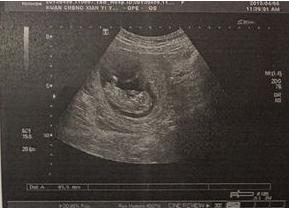

1、看孕早期b超数据

如果胎儿检查长和宽的相差在一倍以上男宝宝可能性大,反之长和宽相等女宝宝可能性大。

2、看孕囊形状

通过看孕囊的形状有可能判断出男女,像茄子或长条状的是男宝宝可能性大,圆圆的是女宝宝可能性大。